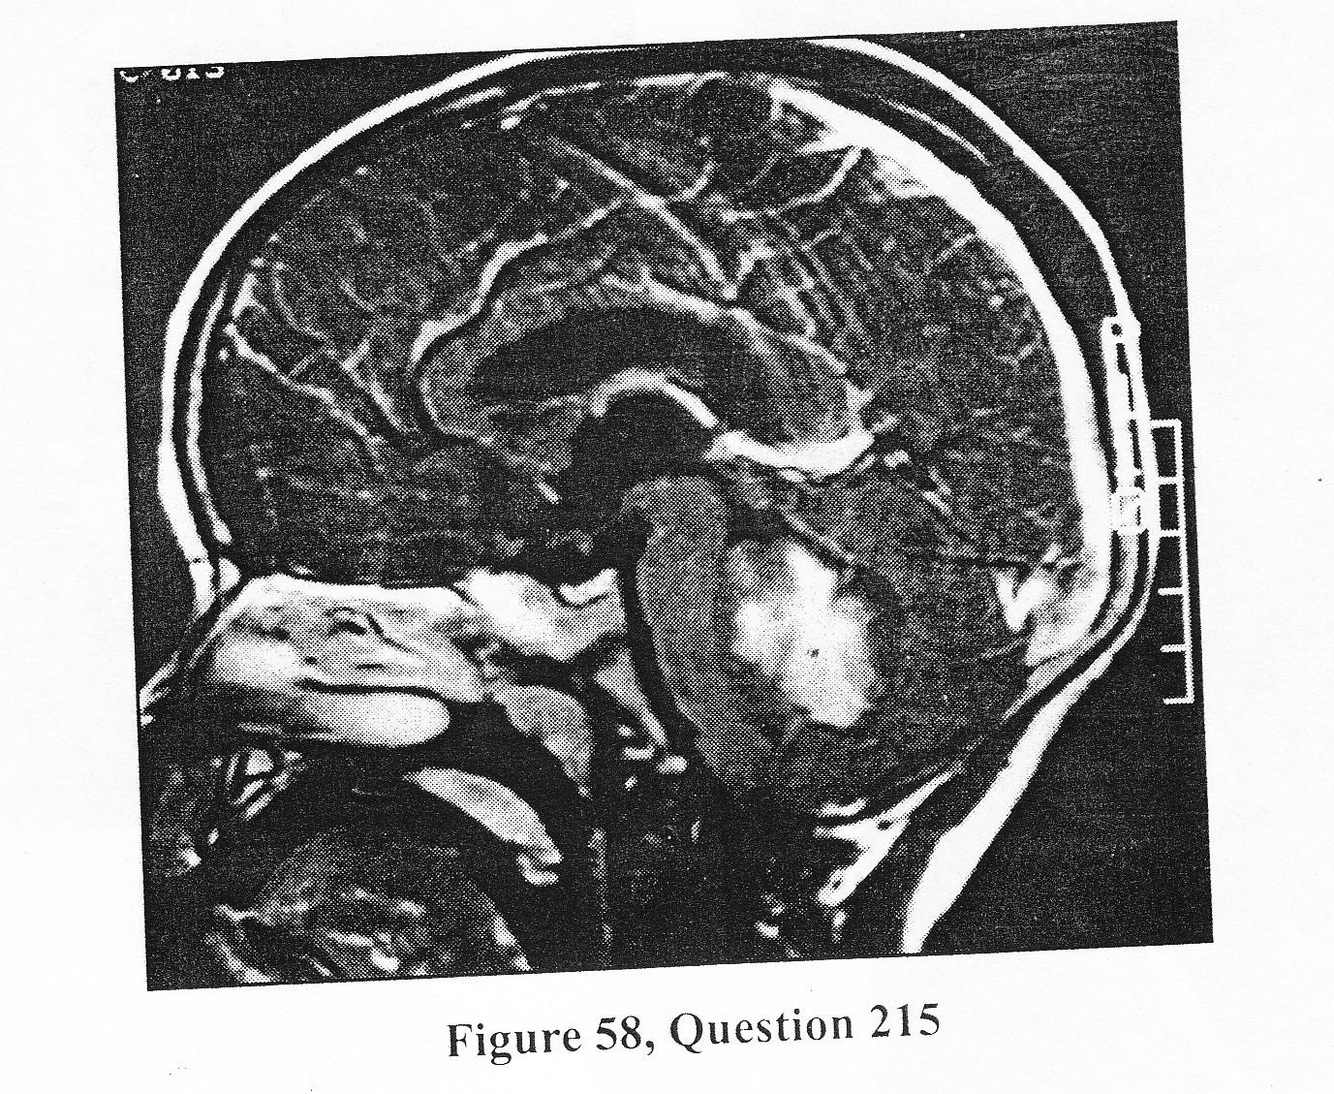

A 5-year-old boy presented with a 3-week history of progressive headache, nausea, vomiting, and blurred vision. On neurologic exam, he had bilateral abducens (CN VI) palsies, papilledema, and mild ataxia. Figure 58 depicts images from an MRI study. 215. Based on the patient’s history, physical, and MR findings, what is the MOST LIKELY diagnosis?

B. medulloblastoma

A 5-year-old boy presented with a 3-week history of progressive headache, nausea, vomiting, and blurred vision. On neurologic exam, he had bilateral abducens (CN VI) palsies, papilledema, and mild ataxia. Figure 58 depicts images from an MRI study. 216. The BEST therapeutic option for this child is

C. both A and B